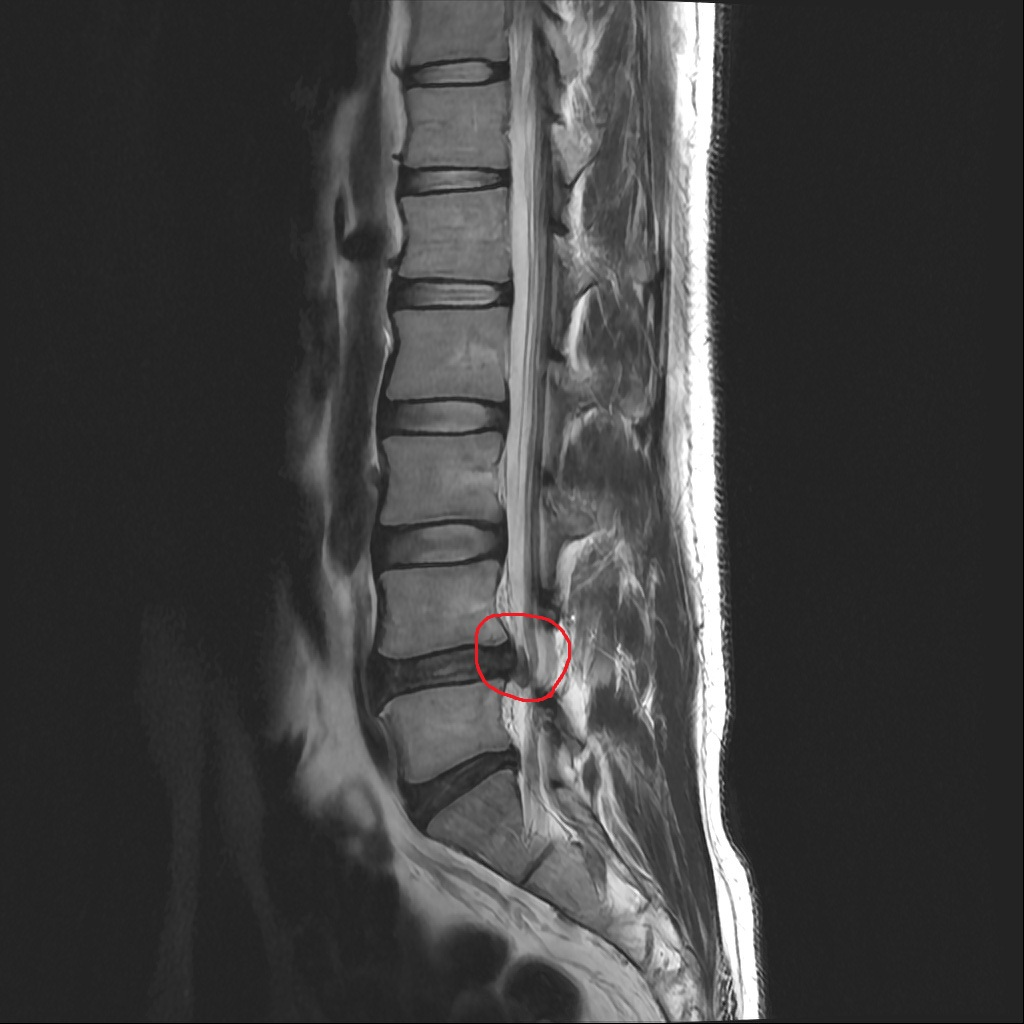

올려주신 MRI 사진상 4번-5번 요추의 디스크 탈출이 있고, 신경도 누르고 있는게 의심됩니다.

올려주신 mri 와 근전도 소견을 종합하면 좌측 L5 신경근이 심하게 압박받고 있으며 신경 손상 증거가 나타납니다.